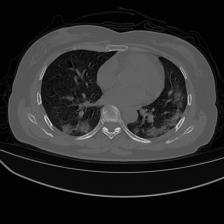

The four visualized examples in Figure 6 are from the binary segmentation experiments of Dataset_2. The first example shows a case in which infection has spread to both lungs and appears as a GGO and small consolidation region at the bottom of the right lung. The comparison between the Unet++ mask and the ground truth (GT) shows that the Unet++ architecture fails in segmenting most of the infection regions. The CopleNet, MISSFormer and UCTransNet masks show improved segmentation performance compared to Unet++. However, these architectures still miss some infected regions or segment lung tissues as infection instead. The mask of our proposed approach shows high similarity with GT in term of the number of regions and their global shape. Both examples 2 and 3 are cases where the infection has a peripheral distribution. The visualized masks show that the proposed D-TrAttUnet is the best architecture consistent with the ground truth. The fourth example depicts a severe case where the infection has spread to most of the lung regions. The visualized masks exhibit that our proposed architecture performs better than the comparison architectures.

Refer to caption Refer to caption Refer to caption Refer to caption Refer to caption Refer to caption Refer to caption

Slice Unet++ CopleNet MISSFormer UCTransNet D-TrAttUnet GT

Figure 6: Visual comparison of a segmentation model trained with different segmentation architectures for Binary Covid-19 segmentation using Dataset_2 and Dataset_3.